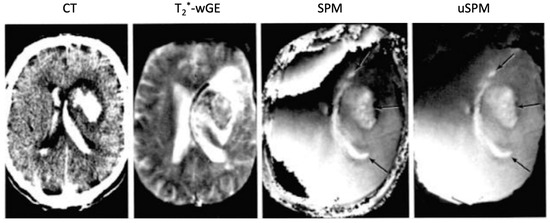

Figure 10.

Intracranial hematomas: CT, heavily T2*-weighted gradient echo (T2*-wGE), susceptibility phase map (SPM) and partly unwrapped SPM (uSPM) 0.15 T (1987) images [12]. The CT image shows the intraparenchymal and ventricular hematomas with high signal. These images show some low signal on the T2*-wGE image. There are specific changes due to susceptibility contrast seen on the SPM and uSPM phase maps (arrows).